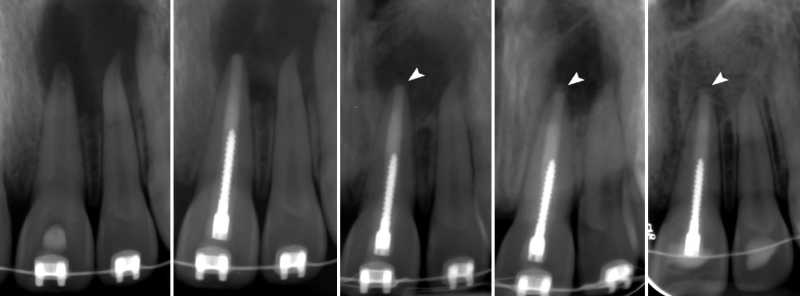

Inicio Especialidades Endodontia